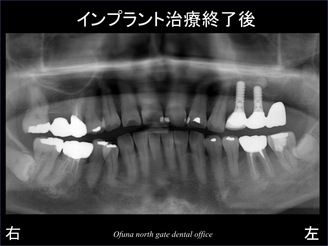

以下のレントゲンは、治療終了後です。

治療終了後の状態に骨吸収を表す線を記入したのが以下のレントゲンです。

インプラントを埋入しなかった奥歯の部分には、骨吸収による穴があるのがわかると思います。